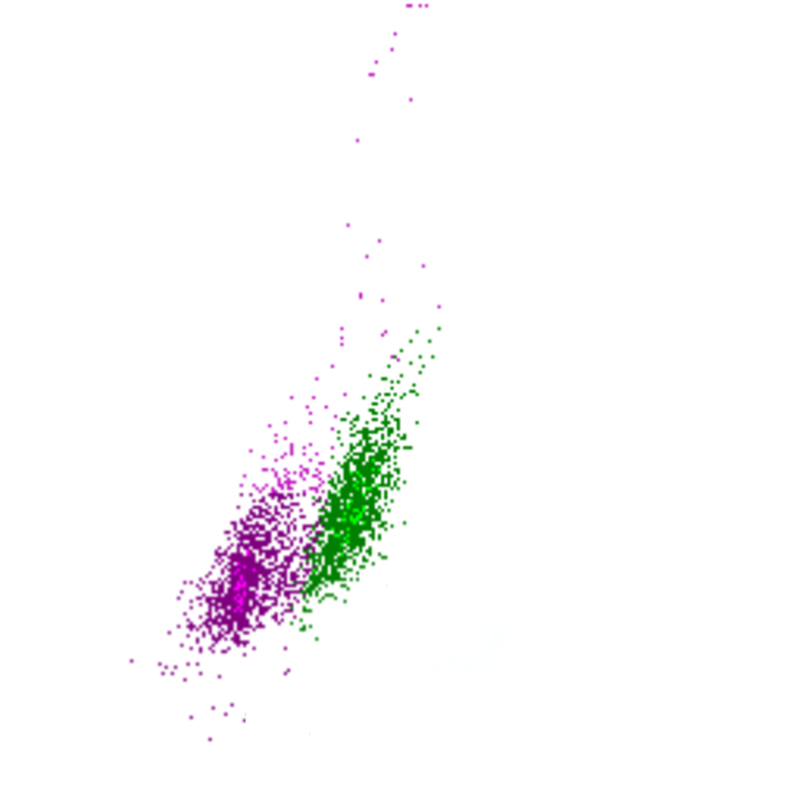

Side Scatter

La complexité cellulaire est principalement déterminée par la présence de structures intracellulaires telles que les granulations. Dans une moindre mesure, la forme du noyau (lobulation) et la présence de vacuoles jouent également un rôle. Dans le canal WDF du Sysmex, les éosinophiles présentent un SSC plus élevé que la normale en raison de l’effet du réactif sur leur granulation.

SSC scatter

SSC faible

SSC élevé